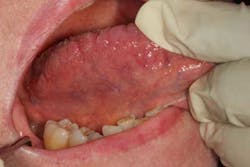

Hard and soft palate: Have the patient open wide and tilt his or her head backward to provide an adequate view of the hard and soft palate. If needed, depress the base of the tongue with a tongue blade to provide a better view of the soft palate. Loose teeth, red spots (figure 3), white spots, ulcerations, rough areas, asymmetry, growths, or other masses may be the first sign of a cancer in this area as in all areas of the head and neck. The uvula should hang down in the midline. Its deviation may indicate a vagal nerve palsy. Some patients have a torus palatinus, or bony outgrowth, from the midline of their hard palate. This variation of normal should not be mistaken for a malignancy.